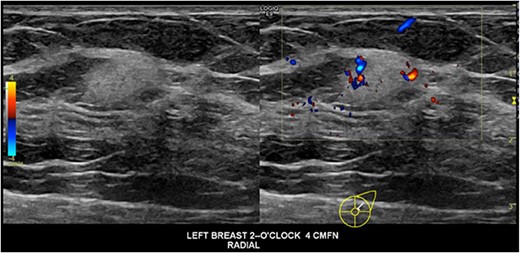

A 40-year-old pregnant female at 8-weeks gestation had an incidental finding of a left breast lesion on investigation for contralateral mastalgia. A mammogram was unremarkable, whilst ultrasound showed a 13 × 9 × 10 mm irregular echogenic lesion with internal vascularity that was within intramammary fat, without connection to the dermal plane (Fig. 1). There were no palpable masses or lymphadenopathy on examination. The patient was otherwise well, with no family history of breast, ovarian cancer or sarcoma.

Ultrasound images of the lesion demonstrating an irregular hyperechoic lesion with internal vascularity.

Given the rarity of intramammary breast DFSPs, they may be mistaken for fibroadenomas or other benign breast masses on imaging. On ultrasound they are usually distinct heterogeneously hyperechoic with hypervascularity on doppler, as seen in our patient. On mammogram these lesions are usually mammographically dense without calcifications or fatty components [3]. Magnetic resonance imaging may be useful with diagnosis, where the lesion will be hypointense to isointense on T1, hyperintense on T2, and rapidly enhancing with contrast, or may mimic fibroadenoma or intramammary lymph node [4].